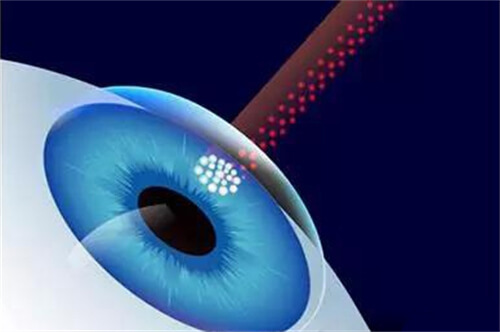

首先,需要明确的是,高度近视1500度并非手术的肯定禁忌。在医学技术不断发展的今天,有多种手术方式可以考虑用于矫正高度近视。其中,眼内屈光手术,特别是人工晶体植入术(ICL),被认为是针对高度乃至***度近视患者的有效选择。

人工晶体植入术(ICL)通过在眼内植入一个特殊的人工晶体来矫正视力,这种手术避免了切削角膜的风险,且对角膜厚度没有严格要求。对于近视度数高达1500度的患者来说,这种手术方式可能更为适合。ICL手术适应的近视度数范围广泛,通常可矫正300度到2300度的近视,以及600度以下的散光。